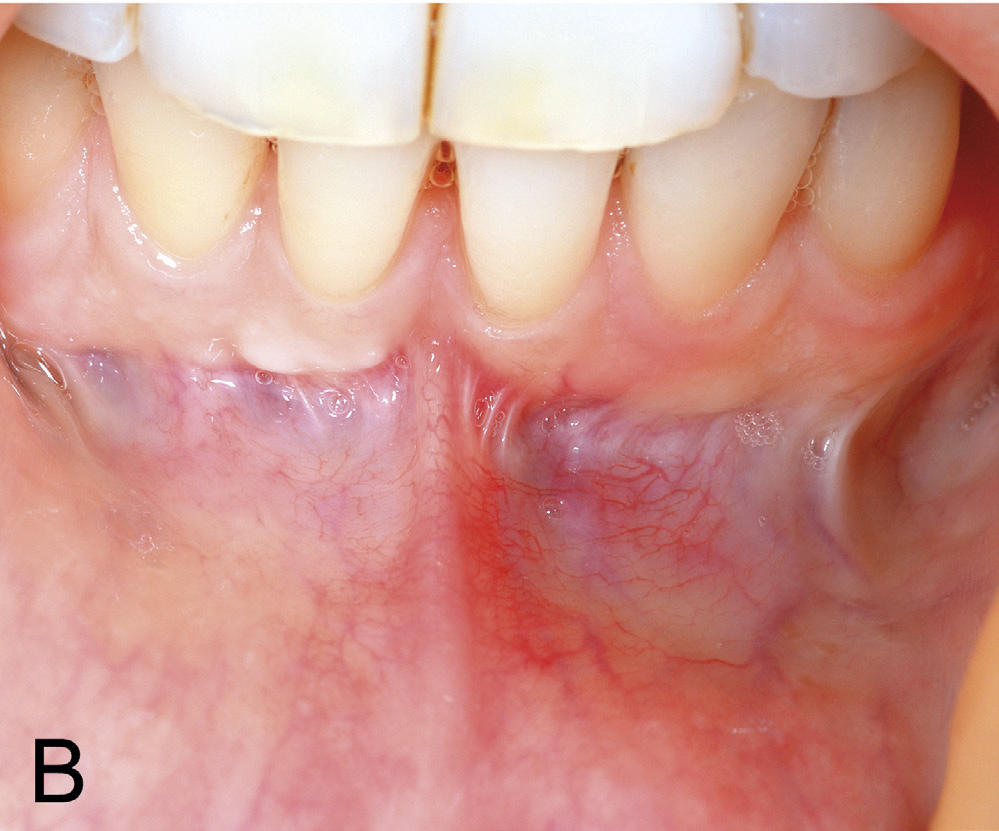

Kasuset er ei kvinne på 31 år, utan kjente sjukdommar eller bruk av legemiddel. Ho fekk utført kjeveortopedisk behandling i tenåra og seinare i 2017 på grunn av residiv. Ei tid etter påsetting av fast apparatur i 2017, merka pasienten ei gradvis utvikling av ein gingival retraksjon lingvalt 41 (figur 1 A). Ved tilvisingstidspunktet, vart pasienten diagnostisert med ein lingval retraksjon på 4 mm i vertikal og 1,5 mm i horisontal retning på 41. Vevstypen vart vurdert som tynn. Akseretninga på 41 vart karakterisert som nøytral utan labial eller lingval tipping. Der var tydeleg drag frå labialt frenulum og med ei smal sone av keratinisert, festa gingiva koronalt for fiberfestet (figur 1 B). Den lingvale defekten vart klassifisert etter Smith sin klassifikasjon (einaste system som klassifiserer lingvale/palatinale retraksjonar). Røntgenbilete av tann 41 viser kort rot utan interdentalt festetap, men med utvida rothinnespalte i apikale halvdel. Incisiven responderte positivt på kuldetest.

Figur 1 B. Frenulumdrag mot margo gingiva regio 31, 41 med ei smal sone av keratinisert, festa gingiva koronalt for fiberfestet.

Basert på kliniske og røntgenologiske funn vart det i begge kjevar bestemt å instruera pasienten i atraumatisk børsteteknikk både lingvalt og labialt. På grunn av usikker prognose ved eit kirurgisk inngrep lingvalt vart det ikkje tilrådd å dekka retraksjonen 41 med eit ganetransplantat. For å redusera risikoen for utvikling av labiale retraksjonar, ville det ha ein førebyggjande effekt å fjerna drag frå frenulum (figur 1 B). Det vart difor bestemt å utføra ein frenektomi med eksisjon av marginale fiberdrag. Under inngrepet vart det diagnostisert ein dehisens labialt på 31 (figur 2 A). Etter eksisjon av periostfesta fiberdrag vart insisjonane freista lukka med seks enkle suturar (figur 2 B). På grunn av brei sårflate koronalt, vart det ikkje oppnådd fullgod sårlukking i festa gingiva. Dette resulterte i ei utilsikta eksponering av beindehisensen 31. Ved første kontroll, 7 dagar postoperativt, var det udekka området delvis lukka med sekundær tilheling. Ved suturfjerning 14 dagar postoperativt var dehisensen på 31 framleis eksponert (figur 3 A). Manglande sårdekning vart freista lukka med to nye suturar. Men ny kontroll etter 1 månad viste auka roteksponering 31 (figur 3 B). Ved postoperativ kontroll etter 1 1/2 månad hadde det marginale blautvevsbandet gått tapt og blautvevsdefekten utvikla seg til ein gingival retraksjon på 4 mm i horisontal og 3 mm i vertikal retning (figur 4).